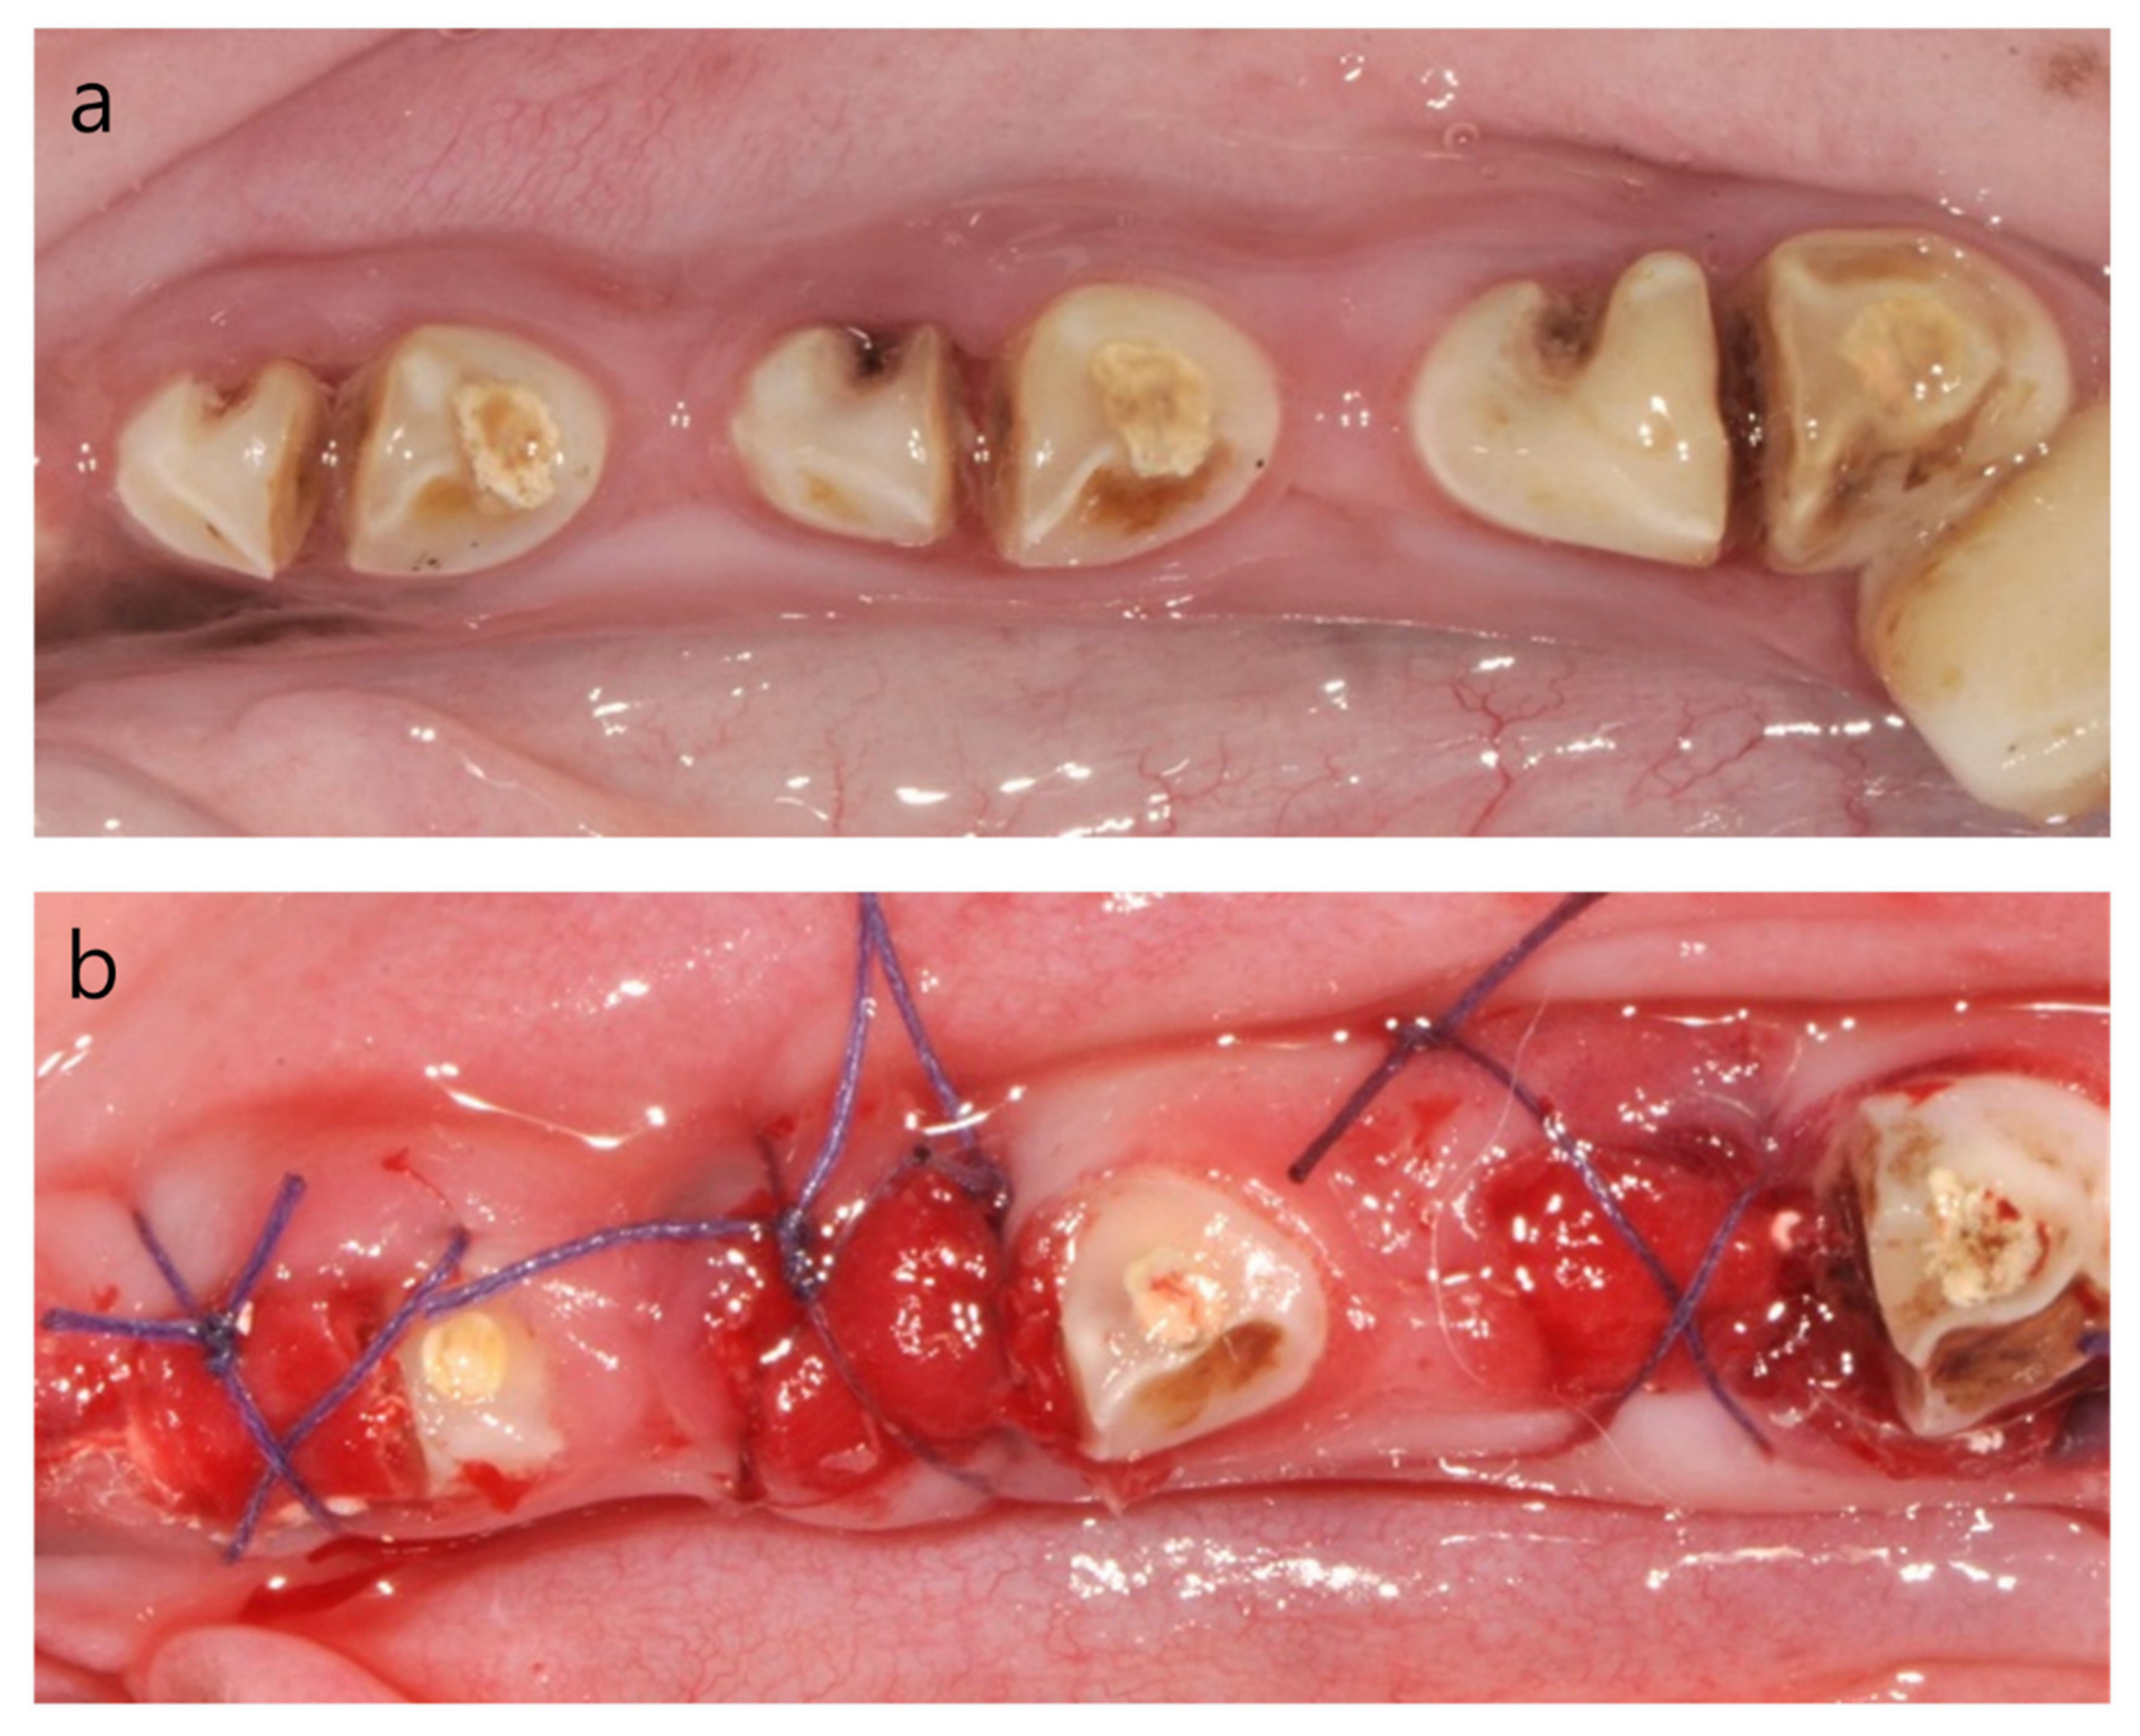

The mesial roots of P2, P3 and P4 were extracted 1 month after the induction of the dehiscence defect with chronic pathology. Three teeth were randomly allocated to the following experimental groups: (i) spontaneous healing without any bone graft (Control group: C); (ii) ridge augmentation with β-TCP granules (Cerasorb, Curasan AG, Kleinostheim, Germany; Test 1 group: T1); and (iii) ridge augmentation with 60% hydroxyapatite (HA) and 40% β-TCP microspheres (HansBiomed, Seoul, Korea; Test 2 group: T2). The granulation tissue was removed thoroughly with a surgical curette after tooth extraction. We applied a double layer of resorbable, non-crosslinked collagen membrane (BioGide®, Geistlich Biomaterials, Wolhusen, Switzerland) at the ridge augmentation site, as previously described [13]. The surgical site was closed with 4/0 Vicryl, and the flap was not mobilized to achieve a primary closure (Figure 3).

Soft-tissue healing was complete at 1-month post-induction of the dehiscence defect with chronic pathology (Figure 3a). Dental plaque accumulated around the surgically created notch area of the mesial root, with resultant inflammation characterized by erythema and edema. When the tooth with chronic pathology was extracted, a marked buccal bone defect was detected by using a probe compared to the lingual bone plate. All extraction sockets in this study showed uneventful healing without any inflammation after the healing period of spontaneous healing/ridge augmentation.

Figure 3. Clinical photographs (a) before extraction and (b) after ridge preservation.